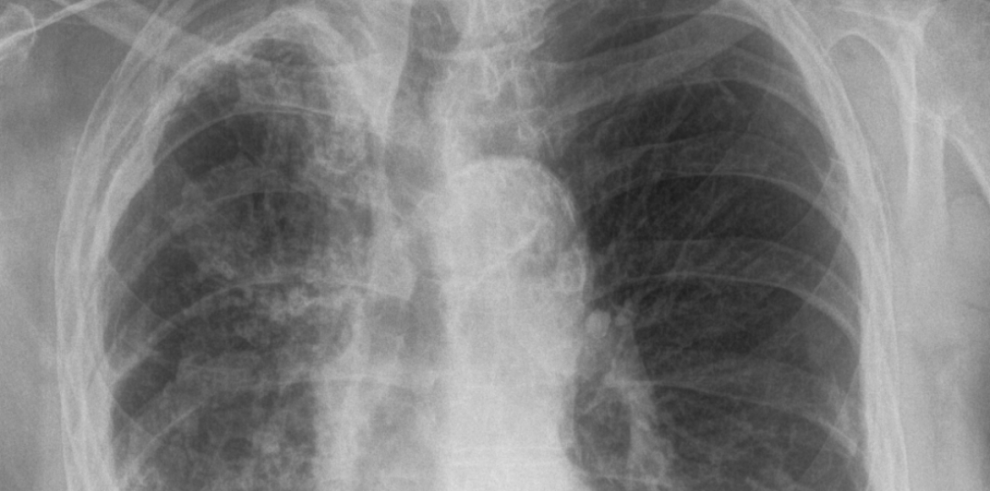

Tuberkuloza je bolest koja se danas dosta lako dijagnosticira. Važno je uzeti dobru anamnezu i obaviti pregled pacijenta, načiniti laboratorijske nalaze i RTG snimak pluća. Analiza biološkog materijala na tuberkuloznu klicu i dalje ostaje prva metoda za postavljanje dijagnoze – kazala je Feni šefica Klinike za plućne bolesti i tuberkulozu “Podhrastovi” KCUS-a prof. dr Belma Paralija, specijalista pneumoftiziolog, bronholog, povodom Sedmice borbe protiv tuberkuloze.

Tuberkuloza (TB) je zarazna bolest uzrokovana lako savijenim, tankim, aerobnim, nepokretnim, štapićastim uzročnikom, koji ne stvara spore, a pripada porodici Mycobacteriaceae. Od svih patogenih vrsta, koje pripadaju Mycobacterium tuberculosis (M. TB) kompleksu, najčešći i najznačajniji uzročnik bolesti kod ljudi je M. tuberculosis. Bolest može zahvatiti bilo koji organ, ali je najčešća lokalizacija u plućima.

Kada osoba oboli od tuberkuloze glavni simptomi su hronični kašalj, subfebrilne temperature, noćno znojenje, gubitak na težini, gubitak apetita, ponekad bol u prsima, a može se javiti i krvav iskašljaj.